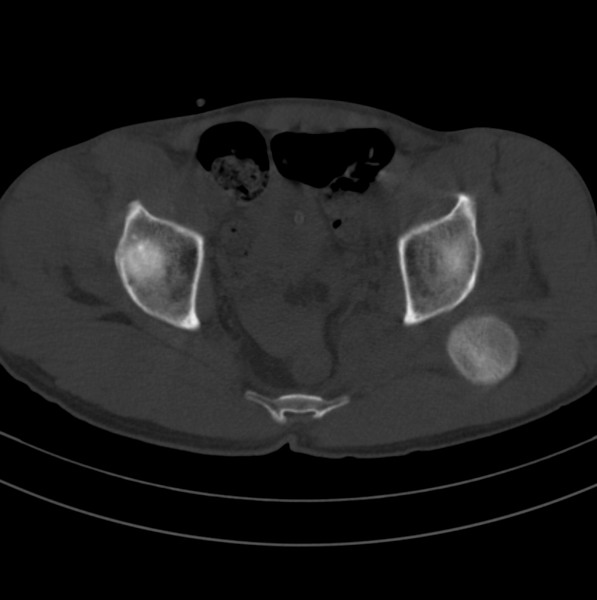

标题: CT18589:股骨头囊状阴影怎么下结论?

男、53

股骨头内的囊状阴影怎么下结论?

左髋关节脱位,其内圆形低密度影,考虑为股骨头疝窝

股骨颈疝窝

一、发病机制

股骨颈疝窝是发生于股骨头基底和股骨颈的一种较少见的良性病变。发病率约在4% 一5% ,好发于中老年人,多无明显症状,常因其他病变检查时偶然发现 。病变多单侧发生,少数为双侧。影像学的正确诊断,可避免不必要的外科手术。

x线平片和ct上多表现为位于股骨头基底和股骨颈近段前侧皮质下、股骨颈中轴线外侧的圆形或卵圆形透亮区或软组织密度灶,边界清楚,多伴有薄层硬化缘。病灶最大径线通常<10 mm。病灶或相邻上下层面上相邻皮质大多可见与病灶相连的局限性裂隙样缺损,可作为诊断此病的特异性征象。病灶内通常为纤维结缔组织和(或)液体。内为液体时,病灶呈均匀长t1、长t2信号。纤维结缔组织和液体同时存在时,病灶于t1wi上呈低信号,t2 wi上呈不均匀高信号。